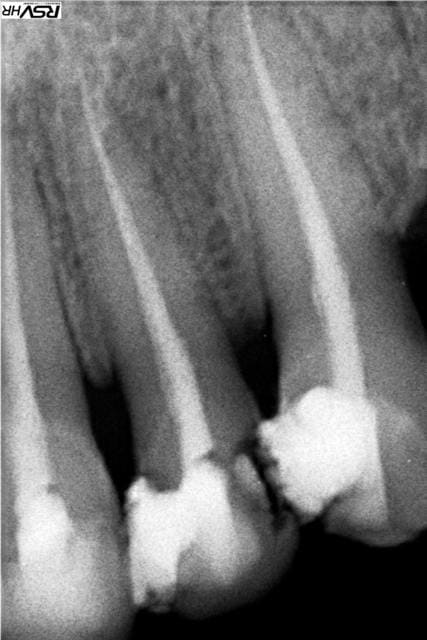

En PJ le dernier specimen, 28 ans, CMU mais dispo que le soir (ben oui il travaille au noir) la bouche en tchernobyl. Je n'ai fait que répondre à sa demande : des dents blanches devant. Pour les extractions allez voir ailleurs.